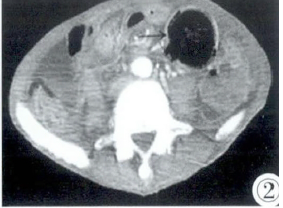

图1,2 CT增强冠状位(图1)及轴位(图2)示空肠近端见5 cm×5 cm×10 cm大小团块影,边界清,其内呈蜂窝状或筛孔状混杂密度及多发气泡影,增强未见明显强化,考虑粪石。其近段十二指肠未见扩张(胃肠减压后)。腹腔见散在小气泡,提示胃肠道穿孔。腹、盆腔见少量积液。